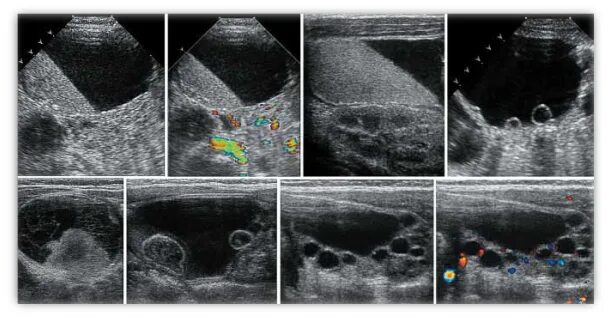

Объемные кистозные образования